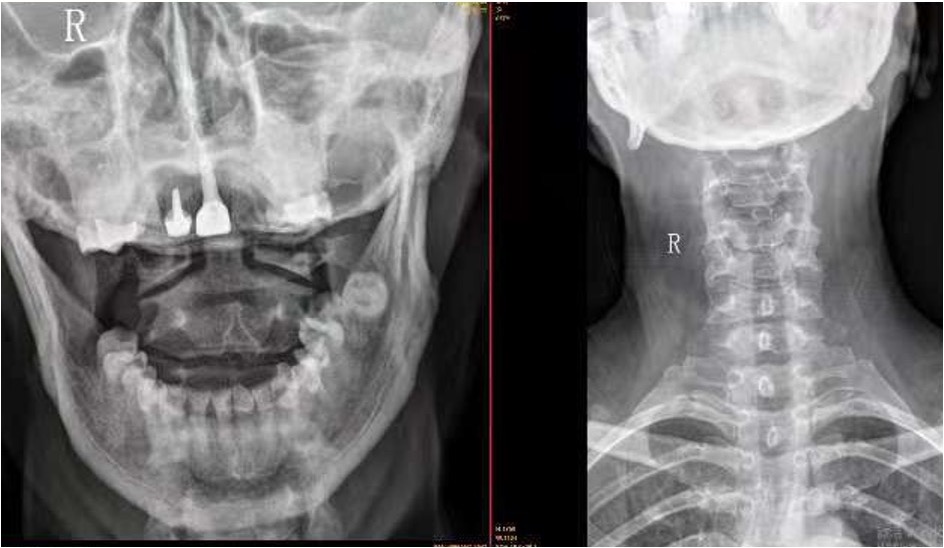

【影像】颈椎X线片报颈椎退行性变,C5椎稍后移位。齿状突与寰椎侧块关节间隙失对称。阅片见颈椎向右侧弯,颈椎平直,C5-6失稳,寰齿侧间隙左侧窄,左侧寰枢外侧关节对合不全,枢椎棘突偏左。

【讨论】患者大椎上方疼痛,查体项僵、肤冷、双侧后斜角肌紧张&压痛(+),X线片颈椎退行性变、向右侧弯、颈椎平直、C5-6失稳,诊断为“颈椎病”。 寰椎左侧横突压痛(+)、右侧头后大直肌紧张&压痛(+),X线片见寰齿侧间隙左侧窄、左侧寰枢外侧关节对合不全、枢椎棘突偏左,诊断为“寰枢关节半脱位”。

患者突然出现头晕、血压升高,无高血压病史,且与颈痛同时出现,考虑“颈源性高血压”。来诊时头晕不重,查体旋颈试验(-),诊断颈源性高血压证据不足。寰枢关节半脱位与颈椎病诊断明确,前者寰椎旋转移位后两侧横突孔分别向前后挤压-牵张椎动脉、C5椎体后移则双侧横突孔向后挤压-牵张椎动脉致椎基底供血不足,引起血压反射性升高。椎基底动脉供血不足则丘脑缺血,影响睡眠-觉醒中枢而睡眠障碍。